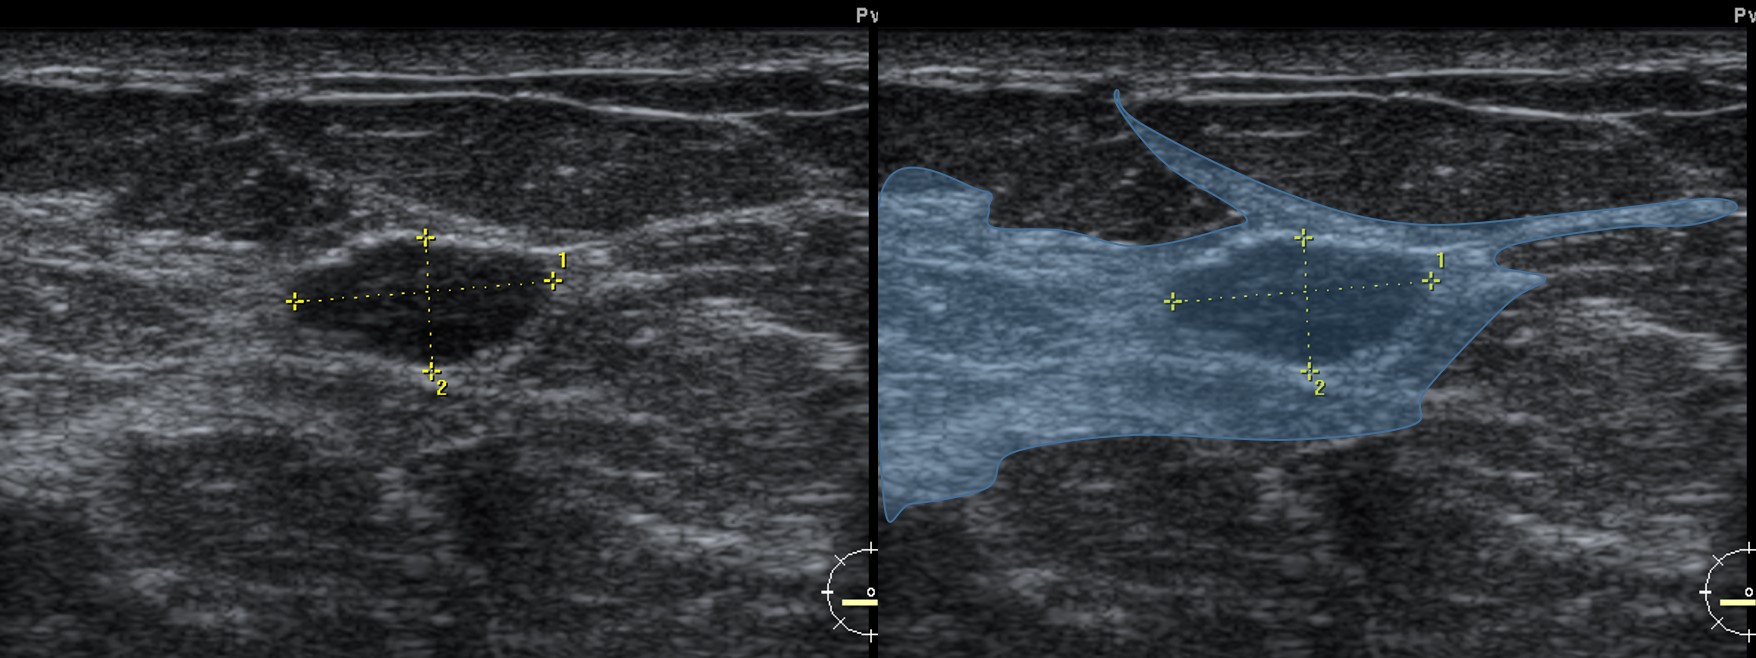

Os lóbulos de gordura mamários são estruturas frequentes e fazem parte da anatomia normal da mama, podendo simular nódulos sólidos à ultrassonografia e constituir fonte tanto de falsos-positivos quanto de falsos-negativos. Cada lóbulo de gordura pode apresentar aspecto nodular em determinados planos de corte, mas geralmente faz parte de uma lâmina contínua de tecido adiposo, em continuidade com a gordura pré-mamária ou retromamária.

Uma característica fundamental é a alta compressibilidade: os lóbulos de gordura são as estruturas mais compressíveis da mama, frequentemente apresentando redução ≥ 30% da dimensão ântero-posterior à compressão com o transdutor, o que constitui forte evidência de natureza adiposa e benignidade (lóbulo de gordura ou lipoma).

Além disso, os lóbulos de gordura não indentam estruturas adjacentes quando comprimidos, ao contrário de nódulos sólidos verdadeiros, como fibroadenomas ou carcinomas, que tendem a deformar tecidos vizinhos.

Frequentemente, os lóbulos de gordura são subdivididos por septos fibrosos finos, visíveis ao ultrassom como linhas ecogênicas retas, geralmente orientadas horizontalmente. Esses septos tornam-se mais evidentes com leve compressão e ajustes finos do posicionamento e do ângulo do transdutor, ajudando a diferenciá-los de nódulos sólidos verdadeiros.